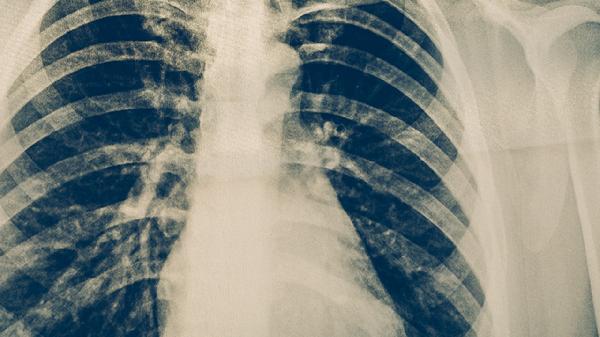

肺結(jié)核復(fù)發(fā)率高嗎?肺結(jié)核,是一種由于結(jié)核菌引發(fā)的肺部感染性疾病,非常威脅人們的身體健康,并且在治療后也不能放松警惕,還要預(yù)防復(fù)發(fā),今天我們一起來看看,肺結(jié)核復(fù)發(fā)率高嗎:

結(jié)核病是由結(jié)核分枝桿菌引起的慢性傳染病,可侵及許多臟器,以肺部結(jié)核感染最為常見。排菌者為其重要的傳染源。人體感染結(jié)核菌后不一定發(fā)病,當(dāng)?shù)挚沽档突蚣?xì)胞介導(dǎo)的變態(tài)反應(yīng)增高時,才可能引起臨床發(fā)病。若能及時診斷,并予合理治療,大多可獲臨床痊愈。